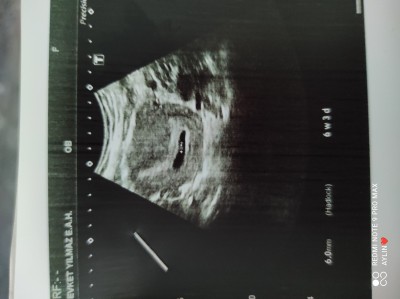

Öncellikle hepinize merhaba arkadaşlar akılımı kurcalayan bazı sorular var. Hamilelikte gebelik kesesi böyle olan var mı ilk hamileliğimde kese böyle değildi. Ve keseyemi bağlı bilmiyorum ama sancılarım çok oluyor

image

Bence kesenin şekli ultrasonun açısına göre farklı görünüyor. İkiz benimki çocuklar aynı kesede ama biri başka diğeri başka görünüyor. Biri yuvarlak gibiyse öteki sanki elips gibi. Halbuki kese aynı kese

Canım o karartı kısım rahim boşluğu ultrason cihazını bastırarak baktıkları zaman öyle oluyor kese bebeği saran bir şey ve biz fotoda net göremiyoruz onu. Bende aynı şekilde endişelenmiştim de doktorum anlatmıştı :)